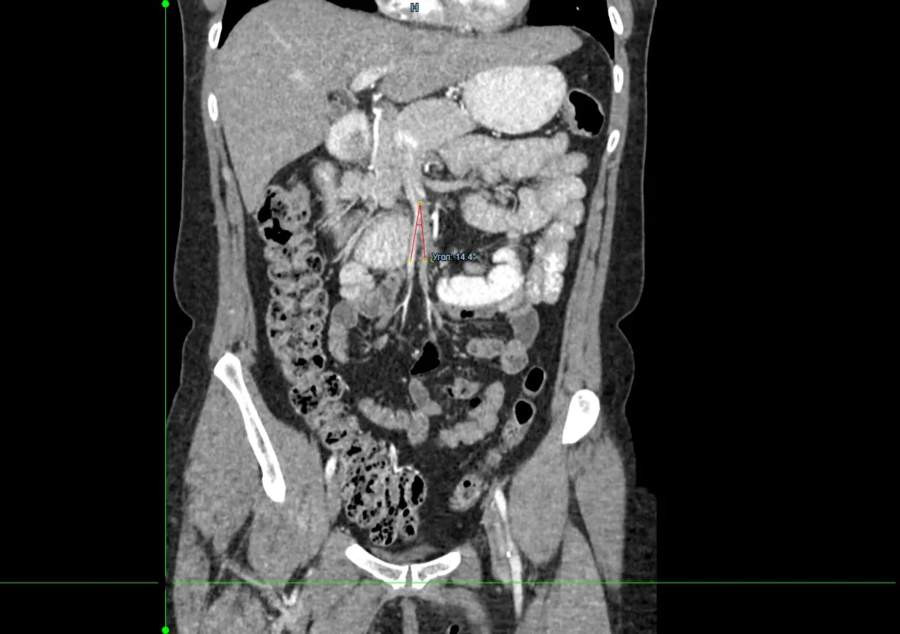

Врачи хирургического отделения № 3 Красноярской межрайонной клинической больницы № 20 имени И. С. Берзона прооперировали 49-летнюю пациентку с редким заболеванием - синдромом Уилки. В мировой литературе описано около 500 таких случаев. Женщина долгое время не могла нормально питаться и сильно похудела.

Хирурги выбрали щадящий метод: выполнена модифицированная операция Стронга в сочетании со скелетерованием и мобилизацией верхней брыжеечной артерии. Это позволило снизить травматичность и сохранить естественную анатомию.